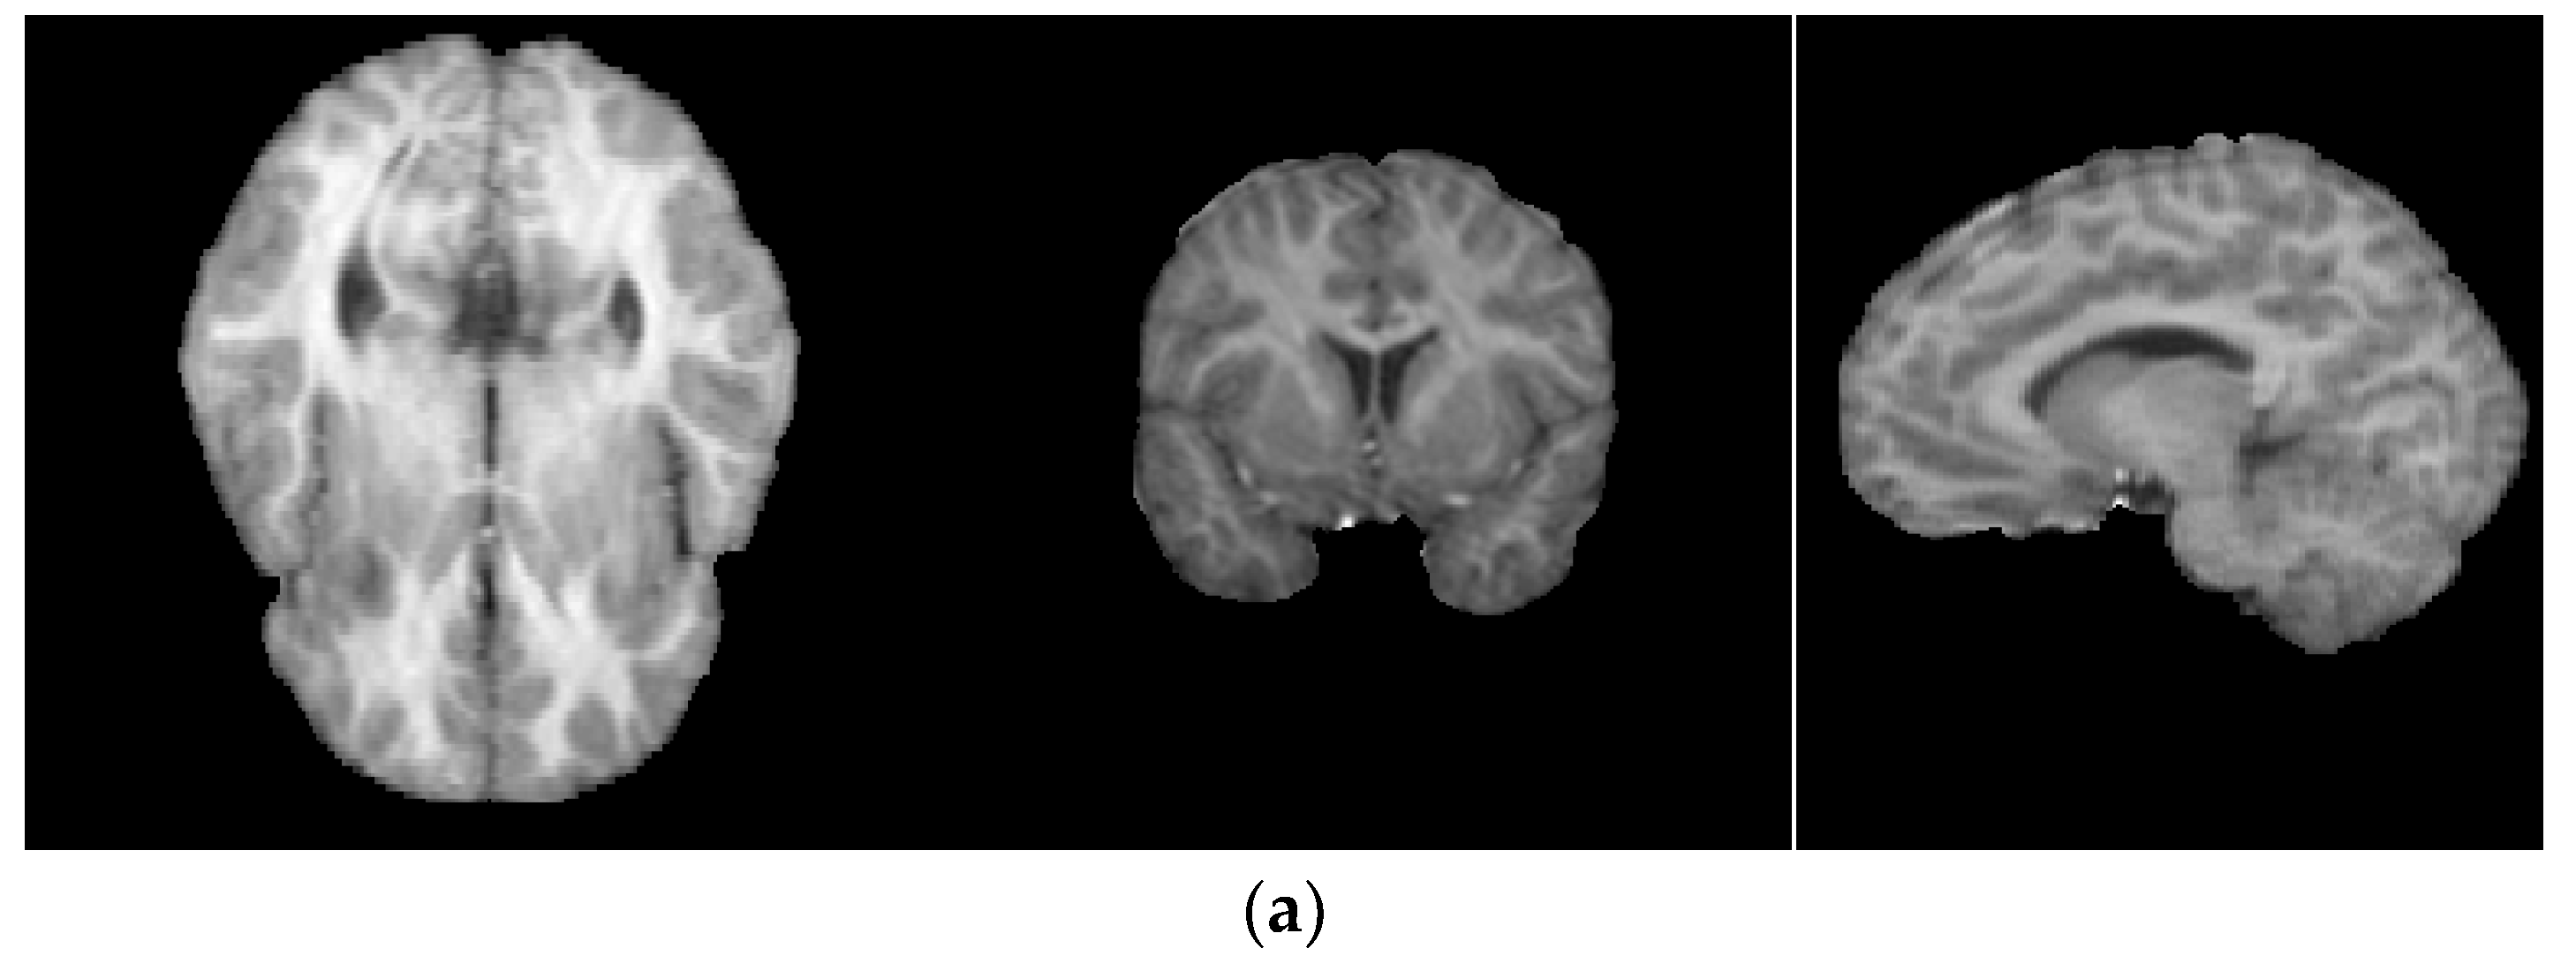

4.3. Real Brain MR Images